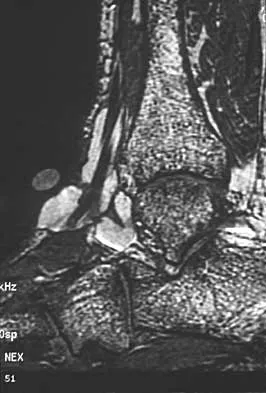

A 16-year-old girl has a painful foot mass. A radiograph, MRI scan, and biopsy specimens are shown in Figures 35a through 35d. What is the most likely diagnosis?